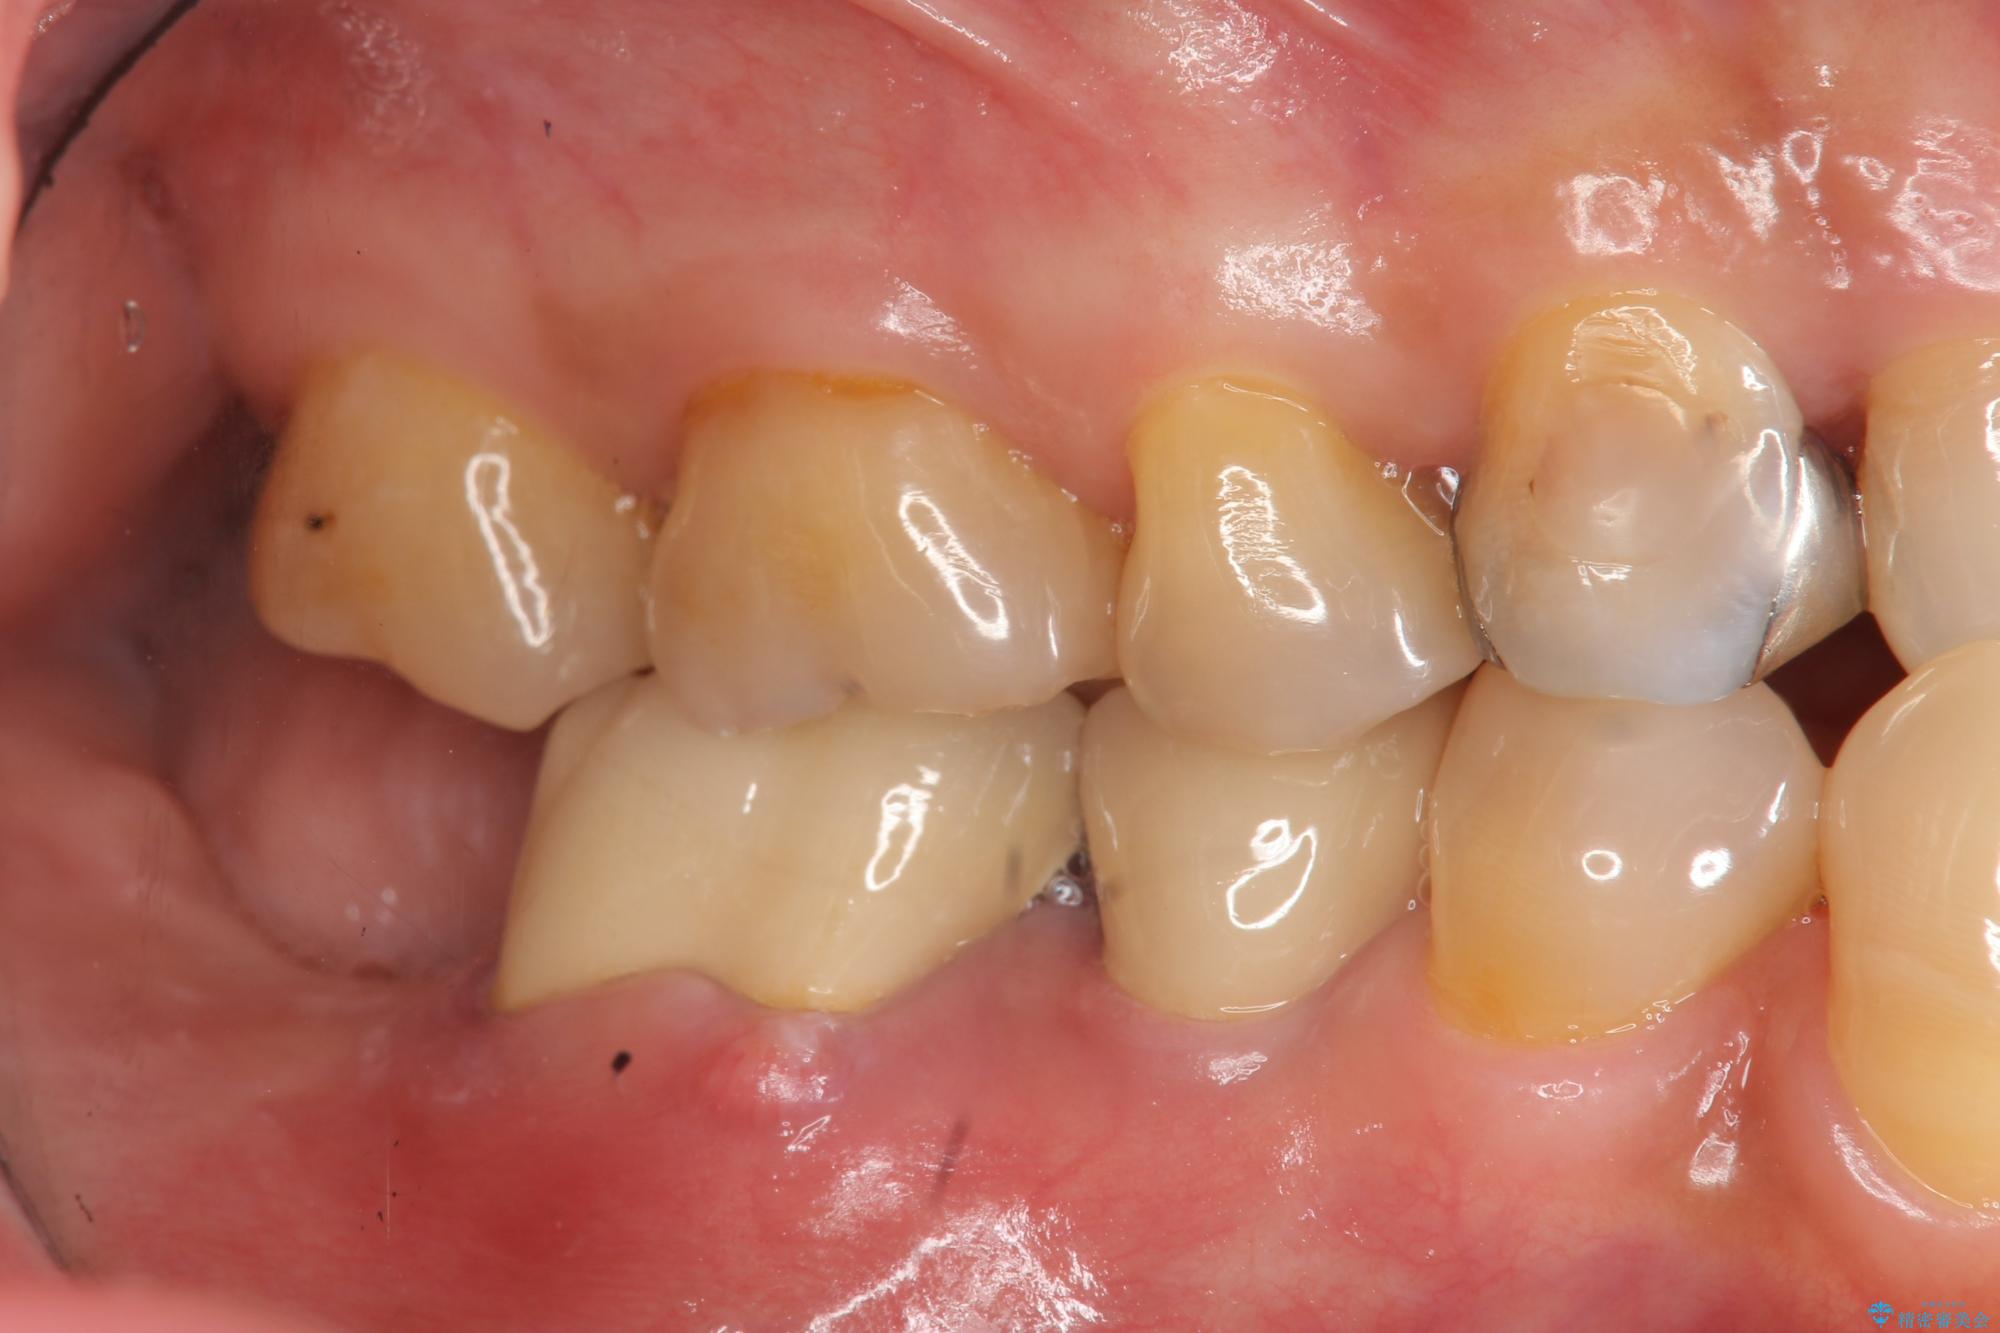

治療後

奥歯から膿のにおいがする インプラントによる機能回復 治療後画像 奥歯から膿のにおいがする インプラントによる機能回復 治療後画像 奥歯から膿のにおいがする インプラントによる機能回復 治療後画像 奥歯から膿のにおいがする インプラントによる機能回復 治療後画像